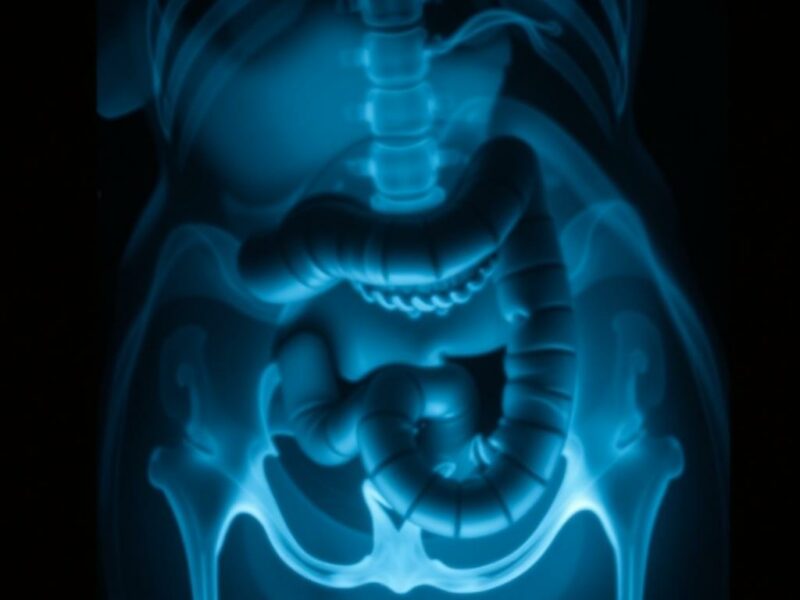

Estudios de imagen

La ecografía abdominal es una herramienta útil, especialmente en niños y embarazadas, porque es rápida y sin radiación. Puede mostrar un apéndice dilatado, líquido alrededor o abscesos. La tomografía computarizada (TC) con contraste es la prueba más sensible y específica: permite visualizar la perforación, la presencia de aire libre en la cavidad abdominal, abscesos y extensión de la infección. La radiografía simple tiene un papel limitado, pero en contextos específicos puede mostrar aire libre si la perforación es franca.